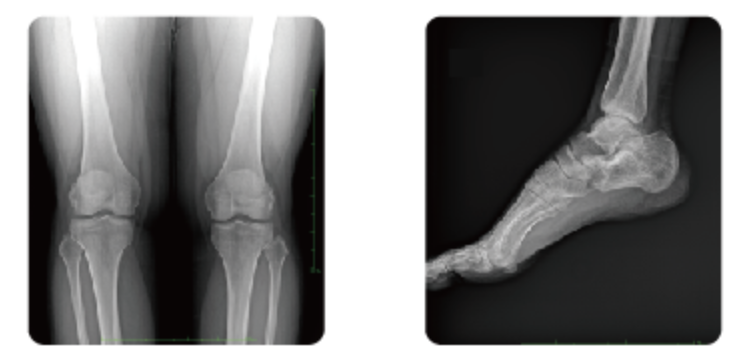

一、典型骨折,有如瓷器被砸碎,裂成了几块,X线照片也能清晰地显示骨折。

二、不典型骨折(隐秘性骨折或不全骨折),就像瓷器轻微受损。出现裂纹,整体外形仍然完整。此时,X线照片常难以显示骨折线,也就极易出现骨折漏诊。经过一段时间,原骨折裂纹的地方长出了新骨,(就像瓷器裂纹修补后的疤痕)。此时拍片才可以发现原来隐藏的骨折。

因此,不典型骨折容易漏诊并非是医生或设备因素造成的,是疾病发展过程决定的。如果伤后局部疼痛明显,拍片又未发现骨折,需要进一步做CT确定,因为CT的敏感性更高,能够发现移位不明显的骨折。

那为什么不一步到位直接做CT检查呢,首先,http://www.pl999.com/class.php?anclss=1&nclass=11骨科X光片检查的价格会更便宜些,而且,X光复查可以把骨折情况,比如对位、对线一目了然,而CT是断层成像,难以低成本的显示骨折整体情况,除非为了检查软组织损伤,所以骨折复查用X光检查比较好,综上所述,骨折通常都会优先去拍骨科X光片。